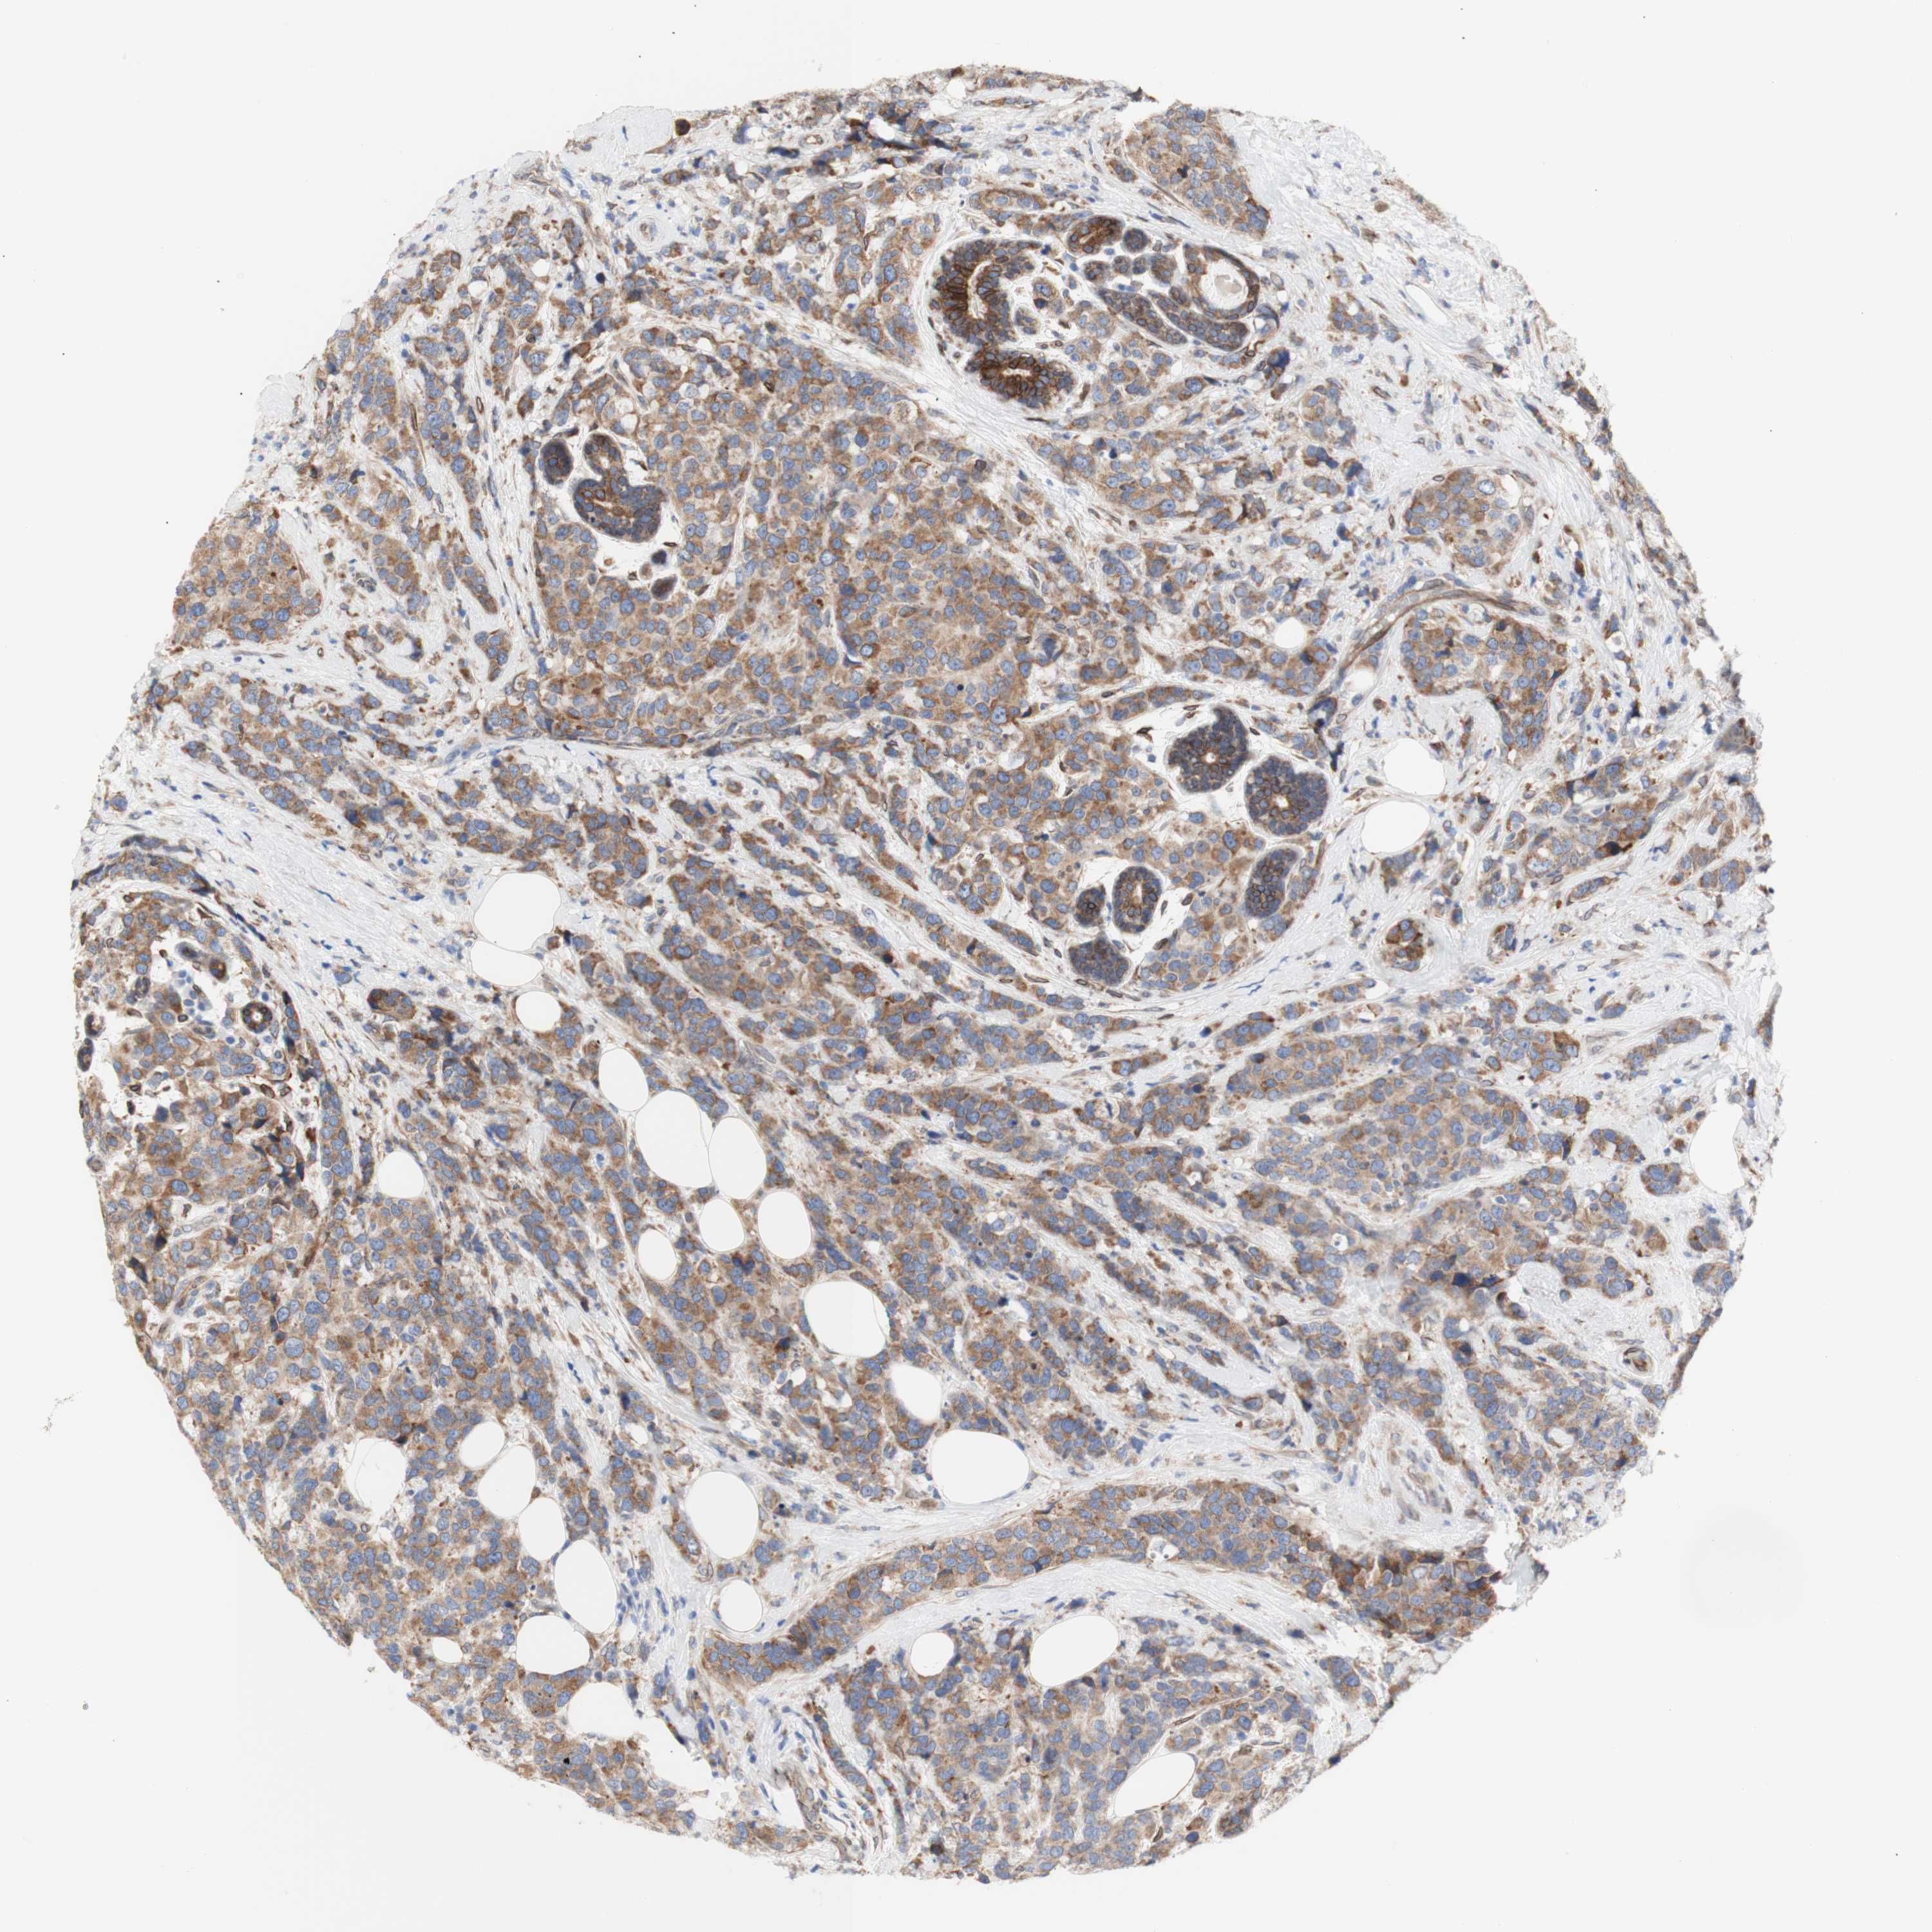

CANCER BREAST CANCER Show tissue menu

BRCA TCGA BRCA VALIDATION PROTEIN EXPRESSION